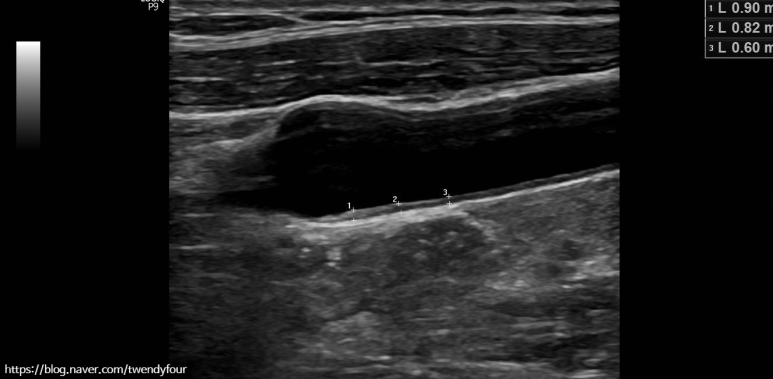

IMT measurement

경동맥 초음파 검사에서 가장 중요한 동맥의 두께를 측정합니다.

경동맥은 내경동맥(ICA;머리로의 혈관), 외경동맥(ECA;얼굴로의 혈관)으로 나뉘는 분지부가 다른 부분보다 굵어지므로 반드시 혈관벽 상태를 측정합니다.

혈관 벽이 두꺼워졌는지 측정합니다.